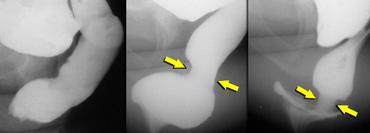

Cần chụp thêm các tư thế chếch hoặc thẳng trước-sau (AP) đối với bất kỳ hình ảnh X-quang nào chưa được giải thích rõ trên tư thế chiếu nghiêng bên (hình minh họa).

Trực tràng hình chữ S có thể giả lồng ruột trên tư thế chiếu nghiêng bên.

Bên trái là tư thế chiếu nghiêng bên và tư thế AP của một bệnh nhân có hình ảnh lồng ruột trên cả hai tư thế chiếu.

Bên trái là tư thế chiếu nghiêng bên và tư thế AP của một bệnh nhân có trực tràng hình chữ S, giả lồng ruột trên tư thế chiếu nghiêng bên.

Đôi khi cần chụp ở tư thế chếch hoặc thẳng trước-sau (AP), vì tư thế AP cung cấp hình ảnh đáng tin cậy hơn về lồng ruột trong ống hậu môn so với tư thế nghiêng tiêu chuẩn trong khi tống phân.